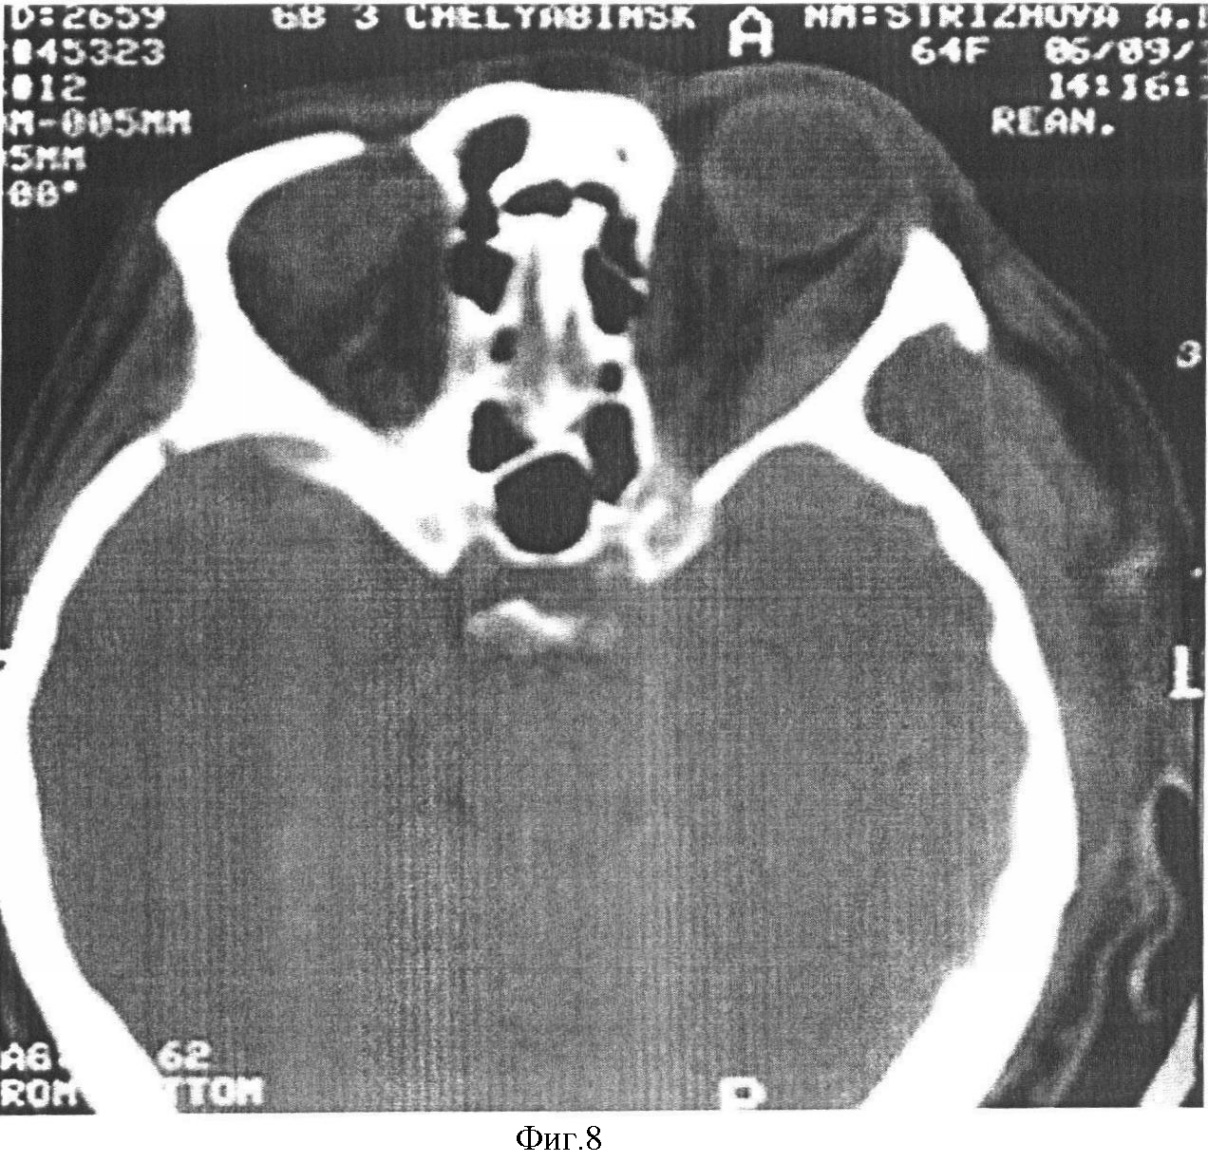

Пример 1: Пациентке Стрижовой А.П., 64 года (ист. болезни 19207, сентябрь 2006 г.), 31 августа удален зуб (6) верхней челюсти. В течение 2 суток повысилась температура до 38°. Появился отек век, легкий экзофтальм. 3 сентября в стоматологической поликлинике выполнена периостотомия верхней челюсти в связи с развившимся гнойным периодонтитом, остеомиелитом. 4 сентября поступила в отделение челюстно-лицевой хирургии с гнойным гаймороэтмоидитом, флегмоной орбиты, щечной, подвисочной области, крылонебной ямки, тромбохом каверзного синуса слева. При поступлении температура 38,5°С, общая слабость, головная боль, тошната, с трудом открывает рот, гнойный экссудат в лунке удаленного зуба, отек верхней переходной складки полости рта, гиперемия кожи, инфильтрат щечной области 6·8 см. OS: visus=0, умеренная гиперемия, отек верхнего и нижнего век, умеренный экзофотальм кпереди (разница со здоровым 3 мм), полная офтальмоплегия, геморрагический хемоз с ущемлением между плотными веками, ДЗН бледно-розовый, четкие границы, артерии сужены, вены умеренно расширены (фиг.7). В крови лейкоцитоз 14,5·109 с нейтрофильным сдвигом влево до 18, повышены моноциты 10%, СОЭ 35 мм/ч, сахар 6,3 ммоль/л, ацетон в моче, гиперкоагуляция. На рентгенограмме черепа обнаружено тотальное затемнение гайморовой пазухи слева. При компьютерной томографии обнаружено образование вдоль нижне-наружной стенки орбиты до вершины 35·9 мм с неоднородным содержимым; деструкции нижней костной стенки орбиты; повышение плотности ретробульбарной клетчатки; уровень жидкости в гайморовой пазухе (фиг.8). Неврологом выявлены ригидность затылочных мышц, симптомы Бабинского, Кернига; в ликворе – белок, нейтрофилы. Через 6 часов с момента поступления произведена операция при совместном участии офтальмолога, оториноларинголога, челюстно-лицевого хирурга: ревизия зоны удаленного зуба, вскрытие и дренирование флегмоны щечной области, подвисочного пространства, кралонебной ямки, гаймороэтмотдотомия, одномоментная орбитотомия со вскрытием и двойным дренированием поднадкостничного пространства, диагностирован субпериостальный абсцесс, выполнена секвестрэктомия нижней стенки орбиты, дренирование субпериостального пространства в гайморову пазуху и наружу, вскрытие ретробульбарной клетчатки (фиг.9, 10). При бактериологическом исследовании выявлен Staphylococcus aureus, Enterococcus faecium. В послеоперационном периоде лечение проводилось в условиях отделения интенсивной терапии с применением антибиотиков широкого спектра (тиенам, цефепим); дезинтоксикационных, антикоагулянтных, сосудистых, ноотропных препаратов (солевые растворы, реополиглюкин, гепарин, фраксипарин, аспирин, пентоксифиллин, ноотропил, актовегин). В течение первой недели гнойная инфекция купирована, снизилась температура, гнойное отделяемое из орбиты исчезло на 5 сутки, дренажи удалены на 9 сутки. 13 сентября наложены вторичные швы на нижнее веко (фиг.11). Через 3 недели полностью восстановилась подвижность глаза, правильное положение глазного яблока и век, глазная щель симметрична.